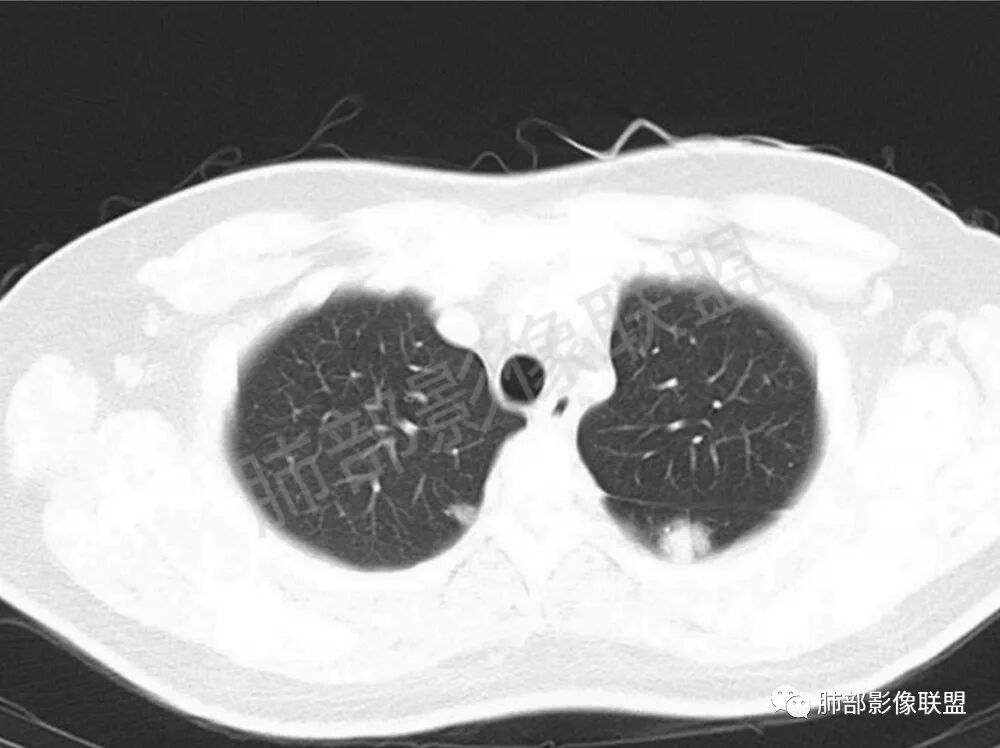

男性,22岁,HIV病史,症状半年,双肺多发大小不等结节影,边缘光滑,密度均匀,以胸膜下分布为主,部分与胸膜相连,胸膜下脂肪间隙可见,病灶近段支气管走行病灶内,远端似有堵塞,无增强图像,考虑隐球菌,鉴别:淋巴瘤,GPA

双肺多发结节影,膨隆,边缘光滑,圆顿,沿支气管血管束分布为主,部分贴胸膜,部分见空洞,空气支气管征

两肺多发结节性,大部分位于胸膜下,部分结节周围可见晕征。局部结节内可见扩张的支气管,纵隔淋巴结大,脾大,22岁男,HIV阳性,常规先考虑隐球菌。鉴别淋巴瘤,结核,马儿。

男,22,半年前咳嗽伴少痰,查HIV阳性,痰查TB阳性,既往有肺部斑片影伴空洞、纵隔淋巴结肿大、脾大。SCC、CA50、CA199、FER增高,此次胸部CT:两肺多发结节影,部分沿血管束分布,部分贴胸膜下,大小不一,密度不一,部分较散、边缘模糊,部分较实、圆钝、周围模糊晕,部分结节有支气管进入穿行自然,部分结节有血管分支自如通过。考虑HI∨相关淋巴增殖类病变,淋巴瘤?LYG?鉴别PC、TB。

1.双肺多发大小不一结节,外围为主,边界尚清,部分周围似有GGO

2.类圆形,部分与胸膜相连,糊墙

3.支气管通畅或近端堵塞